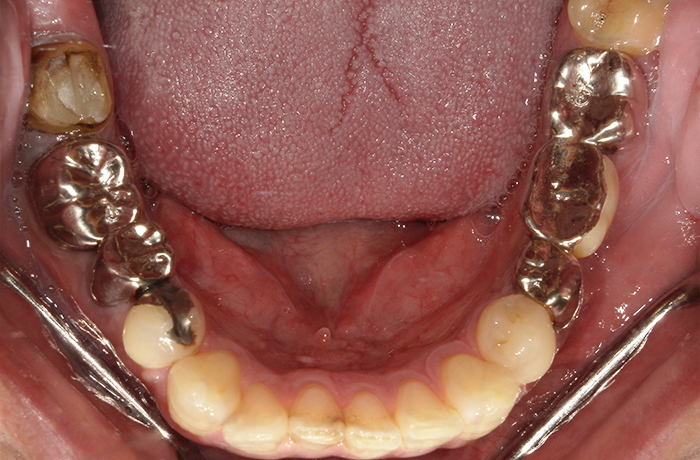

治療後

治療終了後の完成した口腔内と

レントゲン写真

インプラント周囲の骨レベルは安定し、歯肉の厚みとラインも自然に回復しました。

ジルコニアクラウンにより周囲歯と調和した色調を再現し、審美性と機能性の両立を実現することができました。